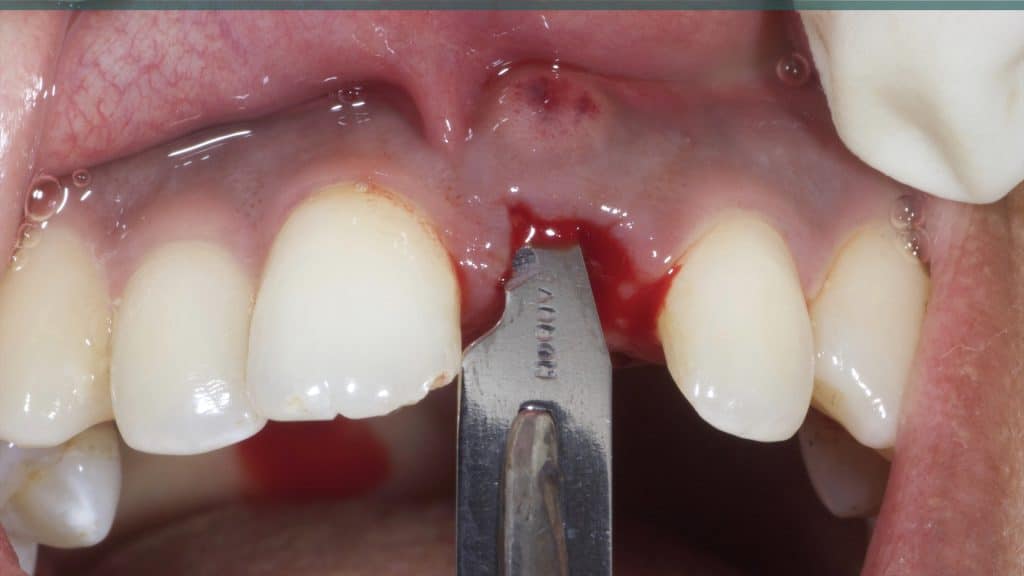

A 27-year female patient with dislodged Resin bonded FPD. She had that FPD for past few years, it had metal wings on palatal surfaces of UR1 and UL2 and a post like metal extension into the root canal of UL1. There was gingival abscess due to fractured root segment most probably due to extended metallic post like structure. Immediate implant placement (IIP) and Immediate restoration (IR) was planned for this patient.

Occlusal check